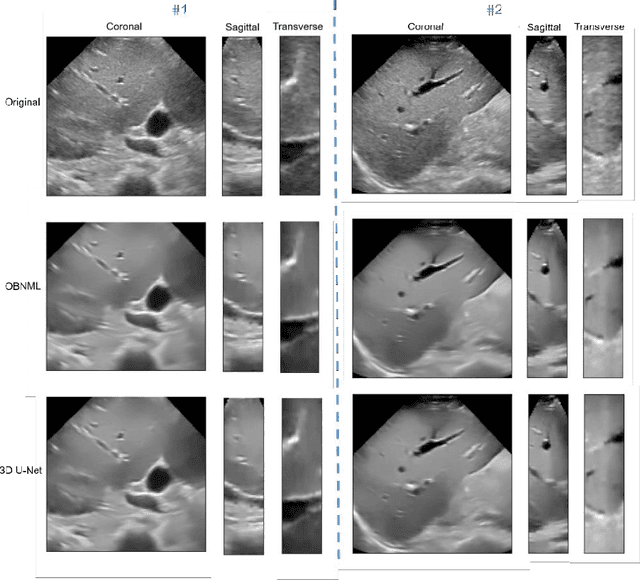

Abstract:Ultrasound (US) speckles are granular patterns which can impede image post-processing tasks, such as image segmentation and registration. Conventional filtering approaches are commonly used to remove US speckles, while their main drawback is long run-time in a 3D scenario. Although a few studies were conducted to remove 2D US speckles using deep learning, to our knowledge, there is no study to perform speckle reduction of 3D B-mode US using deep learning. In this study, we propose a 3D dense U-Net model to process 3D US B-mode data from a clinical US system. The model's results were applied to 3D registration. We show that our deep learning framework can obtain similar suppression and mean preservation index (1.066) on speckle reduction when compared to conventional filtering approaches (0.978), while reducing the runtime by two orders of magnitude. Moreover, it is found that the speckle reduction using our deep learning model contributes to improving the 3D registration performance. The mean square error of 3D registration on 3D data using 3D U-Net speckle reduction is reduced by half compared to that with speckles.